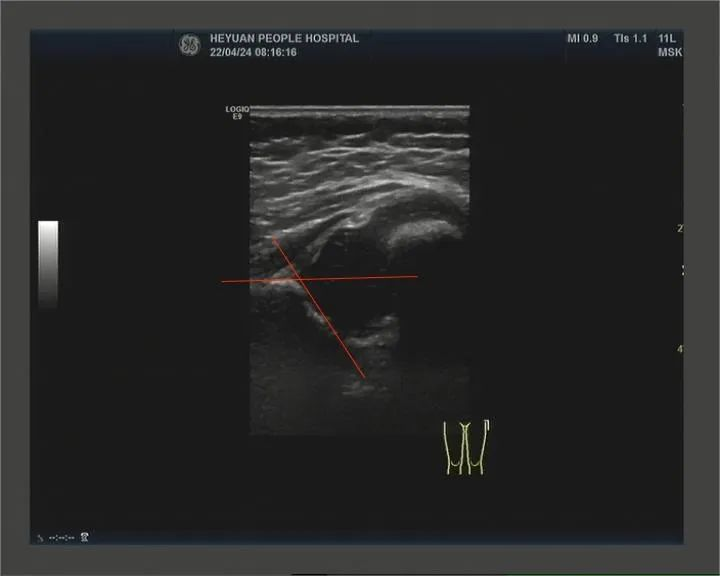

4、婴幼儿先天性髋关节发育不良的早期筛查

婴儿髋关节(Graf 法分型:IIa型)